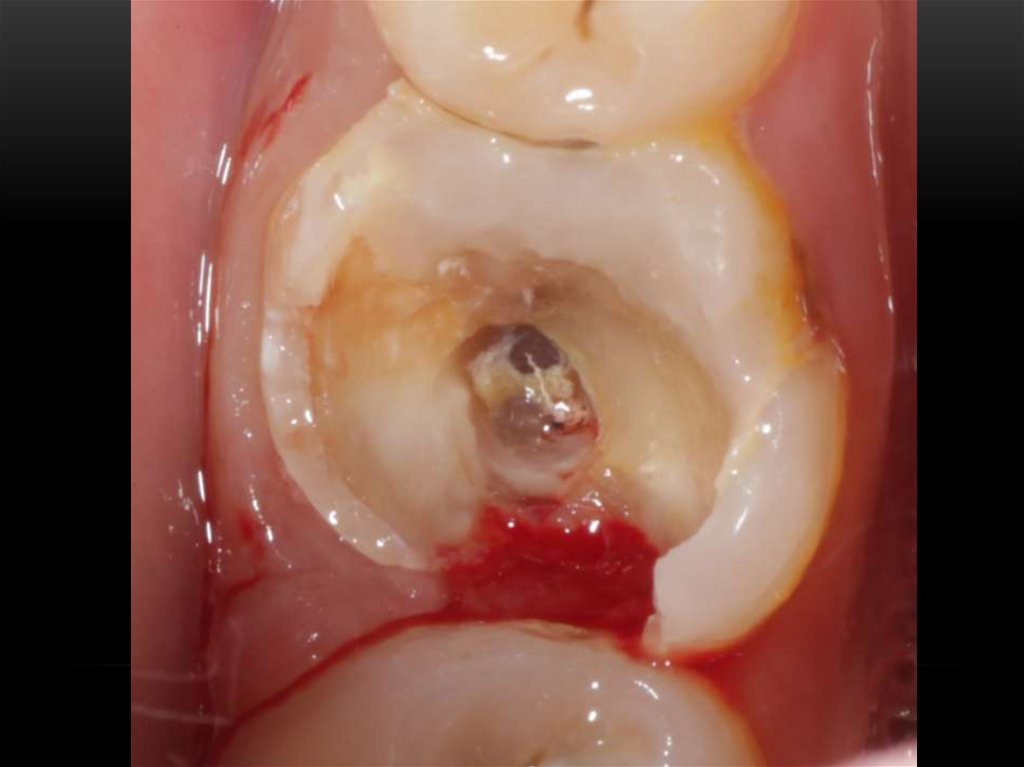

Механическая обработка корневых каналов. Этапы эндодонтического лечения

Принципы препарирования корневых каналов. Алгоритмы эндодонтического лечения

Эндодонтическое лечение зубов. Инструментальная обработка корневых каналов. Лекция 3-4

Ирригации корневых каналов

Методики пломбирования корневых каналов

Лечение корневых каналов